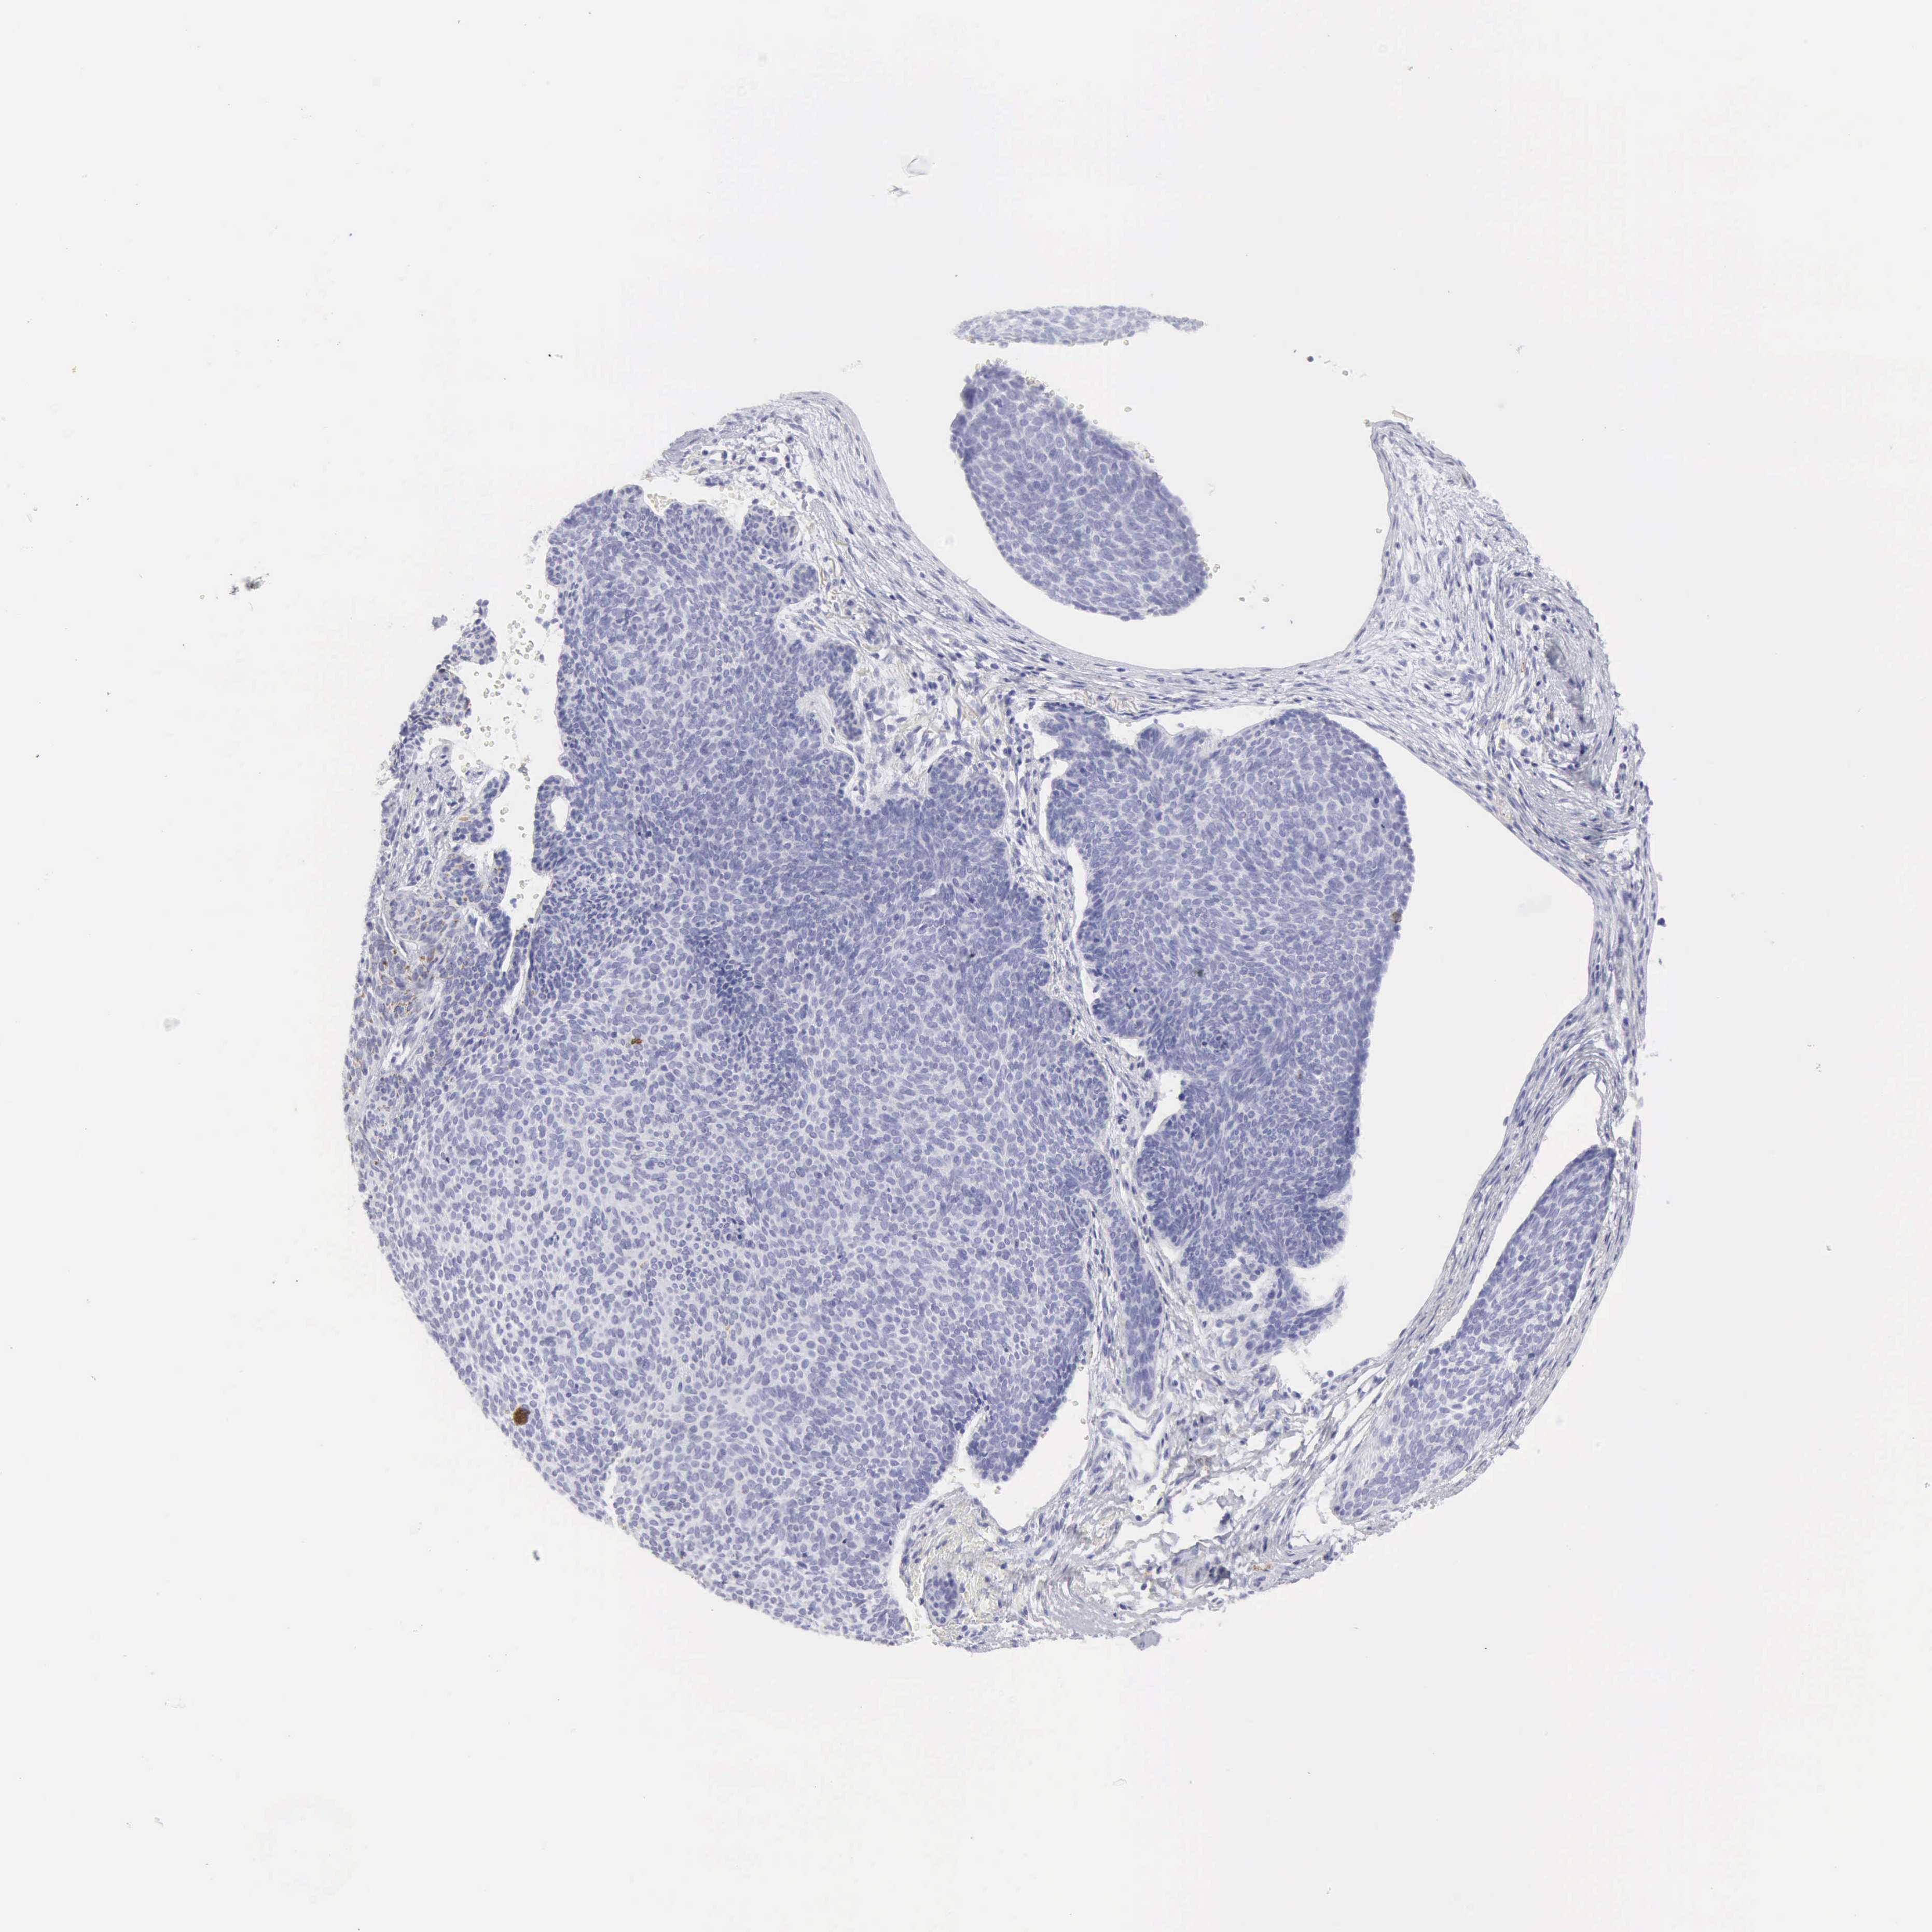

SKIN CANCER - Protein expressioni

A mouse-over function shows sample information and annotation data. Click on an image to view it in a full screen mode. Samples can be filtered based on level of antibody staining by selecting one or several of the following categories: high, medium, low and not detected. The assay and annotation is described here.

Each image is clickable and will lead to virtual microscopy that enables deeper exploration of all samples and also displays staining intensity scores, fraction scores and subcellular localization as well as patient and tissue information for each sample.

Antibody HPA039835

Antibody CAB000142

Antibody CAB018071

Basal cell carcinoma

Squamous cell carcinoma, NOS

Squamous cell carcinoma, metastatic, NOS

Squamous cell carcinoma in situ, NOS

Adnexal tumor, benign